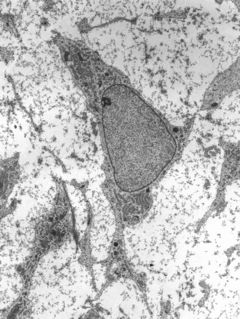

Mezenchymální kmenová buňka

Mezenchymální kmenová buňka (MSC) je multipotentní buňka schopná obnovovat poškozené mezenchymální a krvetvorné tkáně. Je schopná se měnit (diferencovat) na široké spektrum buněčných typů, jako je chondrocyt, adipocyt, osteocyt, osteoblast, myocyt, kardiomyocyt, neuron či inzulin produkující buňka.[1] Mezenchymální buňky jsou proto vhodnými kandidáty pro použití v regenerativní medicíně a buněčné terapii.[1]